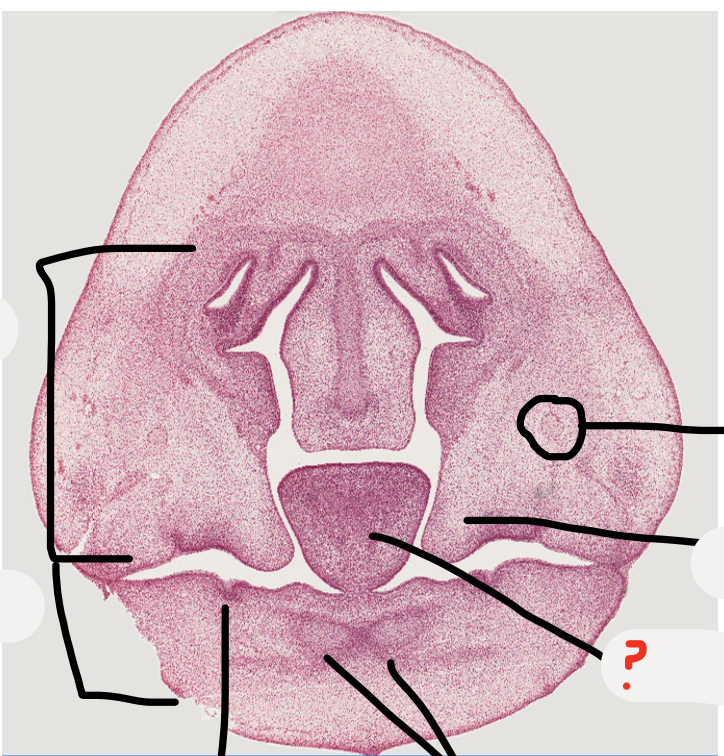

what process is this?

mandibular process

3

5

A

tongue

6

palatal shelves

7

maxillary nerve trunk

8

what is this and its function?

nasal capsule

primitive support

9

dental lamina

10

what is this structure?

nerve trunk

no nuclei in axons as they are in cell bodies that are miles away in the trigeminal ganglion, nuclei we do see are supporting cells

13

predict what age the embryo is, why?

Week 7 as palatal shelves down lateral tongue and tongue takes up most of the space

Week 6 is when see the first evidence of tooth development